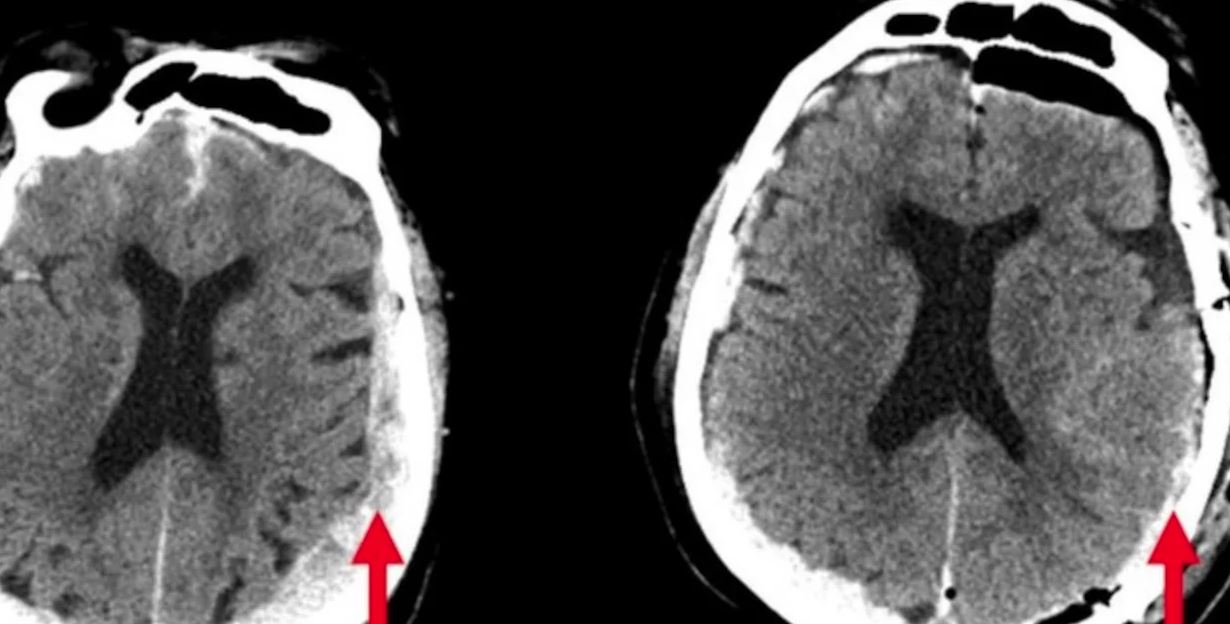

Η έρευνα δημοσιεύθηκε σε επιστημονικό περιοδικό της Νευροεπιστήμης (Frontiers in Ageing Neuroscience) και αφορά στο ηλεκτρικό εγκεφαλογράφημα ενός 87χρονου ασθενούς, ο οποίος απεβίωσε ξαφνικά από καρδιακή ανακοπή.

Πάντως, επειδή ο ασθενής είχε ιστορικό με βλάβες στον εγκέφαλο, οι ερευνητές δέχονται ότι τα δεδομένα τους είναι «πολύπλοκα», ενώ σκοπεύουν να επεκτείνουν τα πειράματά τους, ώστε να επιβεβαιώσουν την έρευνά τους.